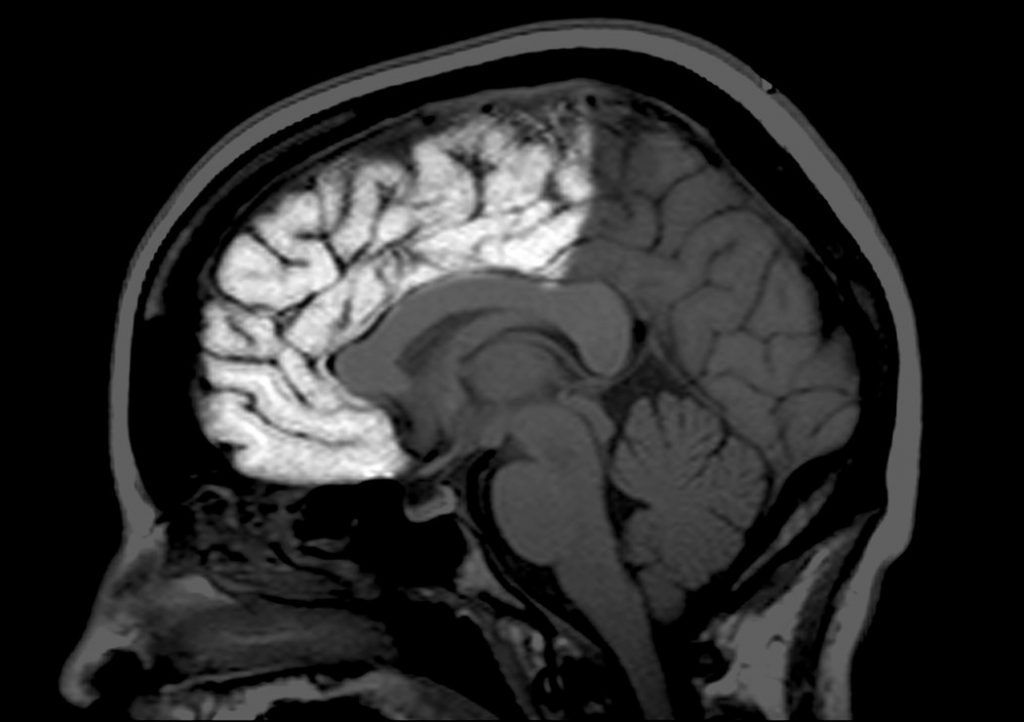

En un artículo de la neurocientífica publicado en la revista Neuron se indica que el cerebro humano alcanza su tamaño adulto a los diez años, pero que las neuronas siguen cambiando por años, en los que las conexiones entre las neuronas se reducen y surgen nuevos vínculos entre zonas separadas del cerebro.

En algún punto, dicha recomposición se vuelve más lenta, lo que indica que el cerebro está madurando, aunque esto sucede a distintos ritmos en diversas partes del cerebro. De este modo, en el lóbulo occipital termina a los 20 años, mientras que en el frontal continúan formándose conexiones nuevas a los 30 años e incluso después.

Al cambiar la anatomía del cerebro, su actividad lo hace también, por lo que en la niñez las regiones colindantes suelen trabajar juntas, mientras que en la edad adulta, las regiones distantes empiezan a actuar en conjunto.

De acuerdo con los neurocientíficos, esta armonía a larga distancia posibilita que el cerebro adulto procese más información y funcione con más eficientemente. Hasta la fecha sigue siendo un misterio el desarrollo de esas redes y cómo influyen en el comportamiento.